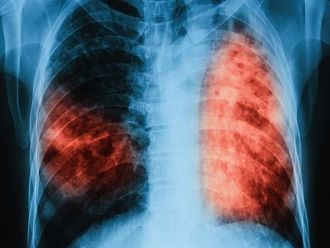

Туберкулозата е лечима и предотвратима, стига да бъде открита навреме и да бъде проведено качествено лечение, припомнят от МЗ.